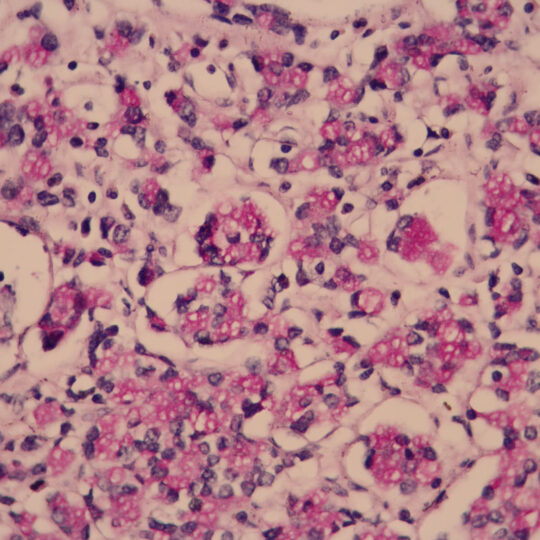

Na bioptickom úseku sa vykonáva štandardná diagnostika nádorových a nenádorových lézií rôznych orgánov, počnúc ochoreniami gastrointestinálneho traktu, ženského a mužského pohlavného systému, močového systému, ochorení hlavy a krku, nádorových ochorení CNS, kože, mäkkých tkanív a štítnej žľazy. Vyšetruje sa fixovaný materiál s použitím štandardných (HE), špeciálnych (Fe, PAS, Melaním VG, Ret…) a imunohistochemických farbiacich metód.

Základom bioptickej diagnostiky je mikroskopické vyšetrenie tkanív, ktoré musia byť spracované na rezy tenké niekoľko mikrometrov. Túto činnosť zabezpečuje bioptické laboratórium. Od kvality jeho práce vo veľkej miere závisí aj kvalita konečnej diagnostiky. Ide o pomerne náročnú procedúru vyžadujúcu čas a profesionálnu zručnosť.

Celý proces sa začína fixáciou tkanív vložením do fixačného média už na oddelení, kde bola vzorka odobratá. Fixácia trvá približne 24 hod. Jej cieľom je konzervovanie tkanív, zabránenie ich rozkladu enzýmami (ktoré sa uvoľňujú po smrti bunky), zachovanie štruktúry tkaniva a jeho farbiacich vlastností. Ďalší deň po odbere a fixácii nasleduje vyšetrenie materiálu lekárom, popis orgánu a odber vzoriek, tzv. excízií. Nasleduje odvodnenie tkaniva a presýtenie parafínom. Túto činnosť vykonávajú špeciálne prístroje – tkanivové procesory, ktoré pracujú automaticky, v poobedňajších a v nočných hodinách. Na tretí deň sa vzorky zalievajú do parafínových blokov, nasleduje ich rezanie, farbenie a montovanie na podložné sklíčka.